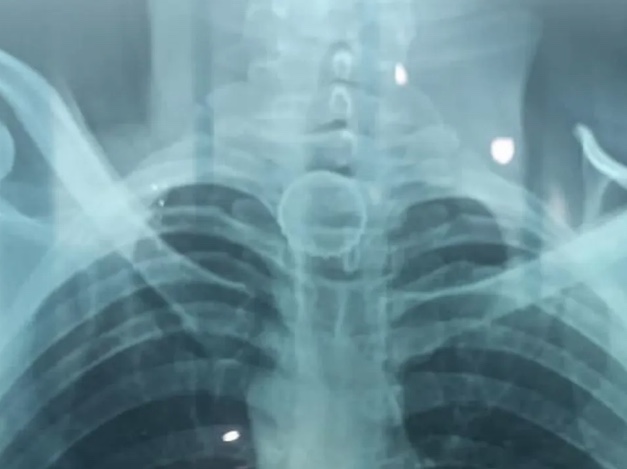

Após engolir a tampa, o homem começou a passar mal e precisou ser transferido para o Hospital do Juruá, em Cruzeiro do Sul, no Acre, onde foram realizados exames e foi constatado que a tampa estava impactada no esôfago.

O objeto foi tirado por volta de 21h, com sucesso, sem sangramento, sem lesão no esôfago, sem perfuração, e o paciente já teve alta médica.